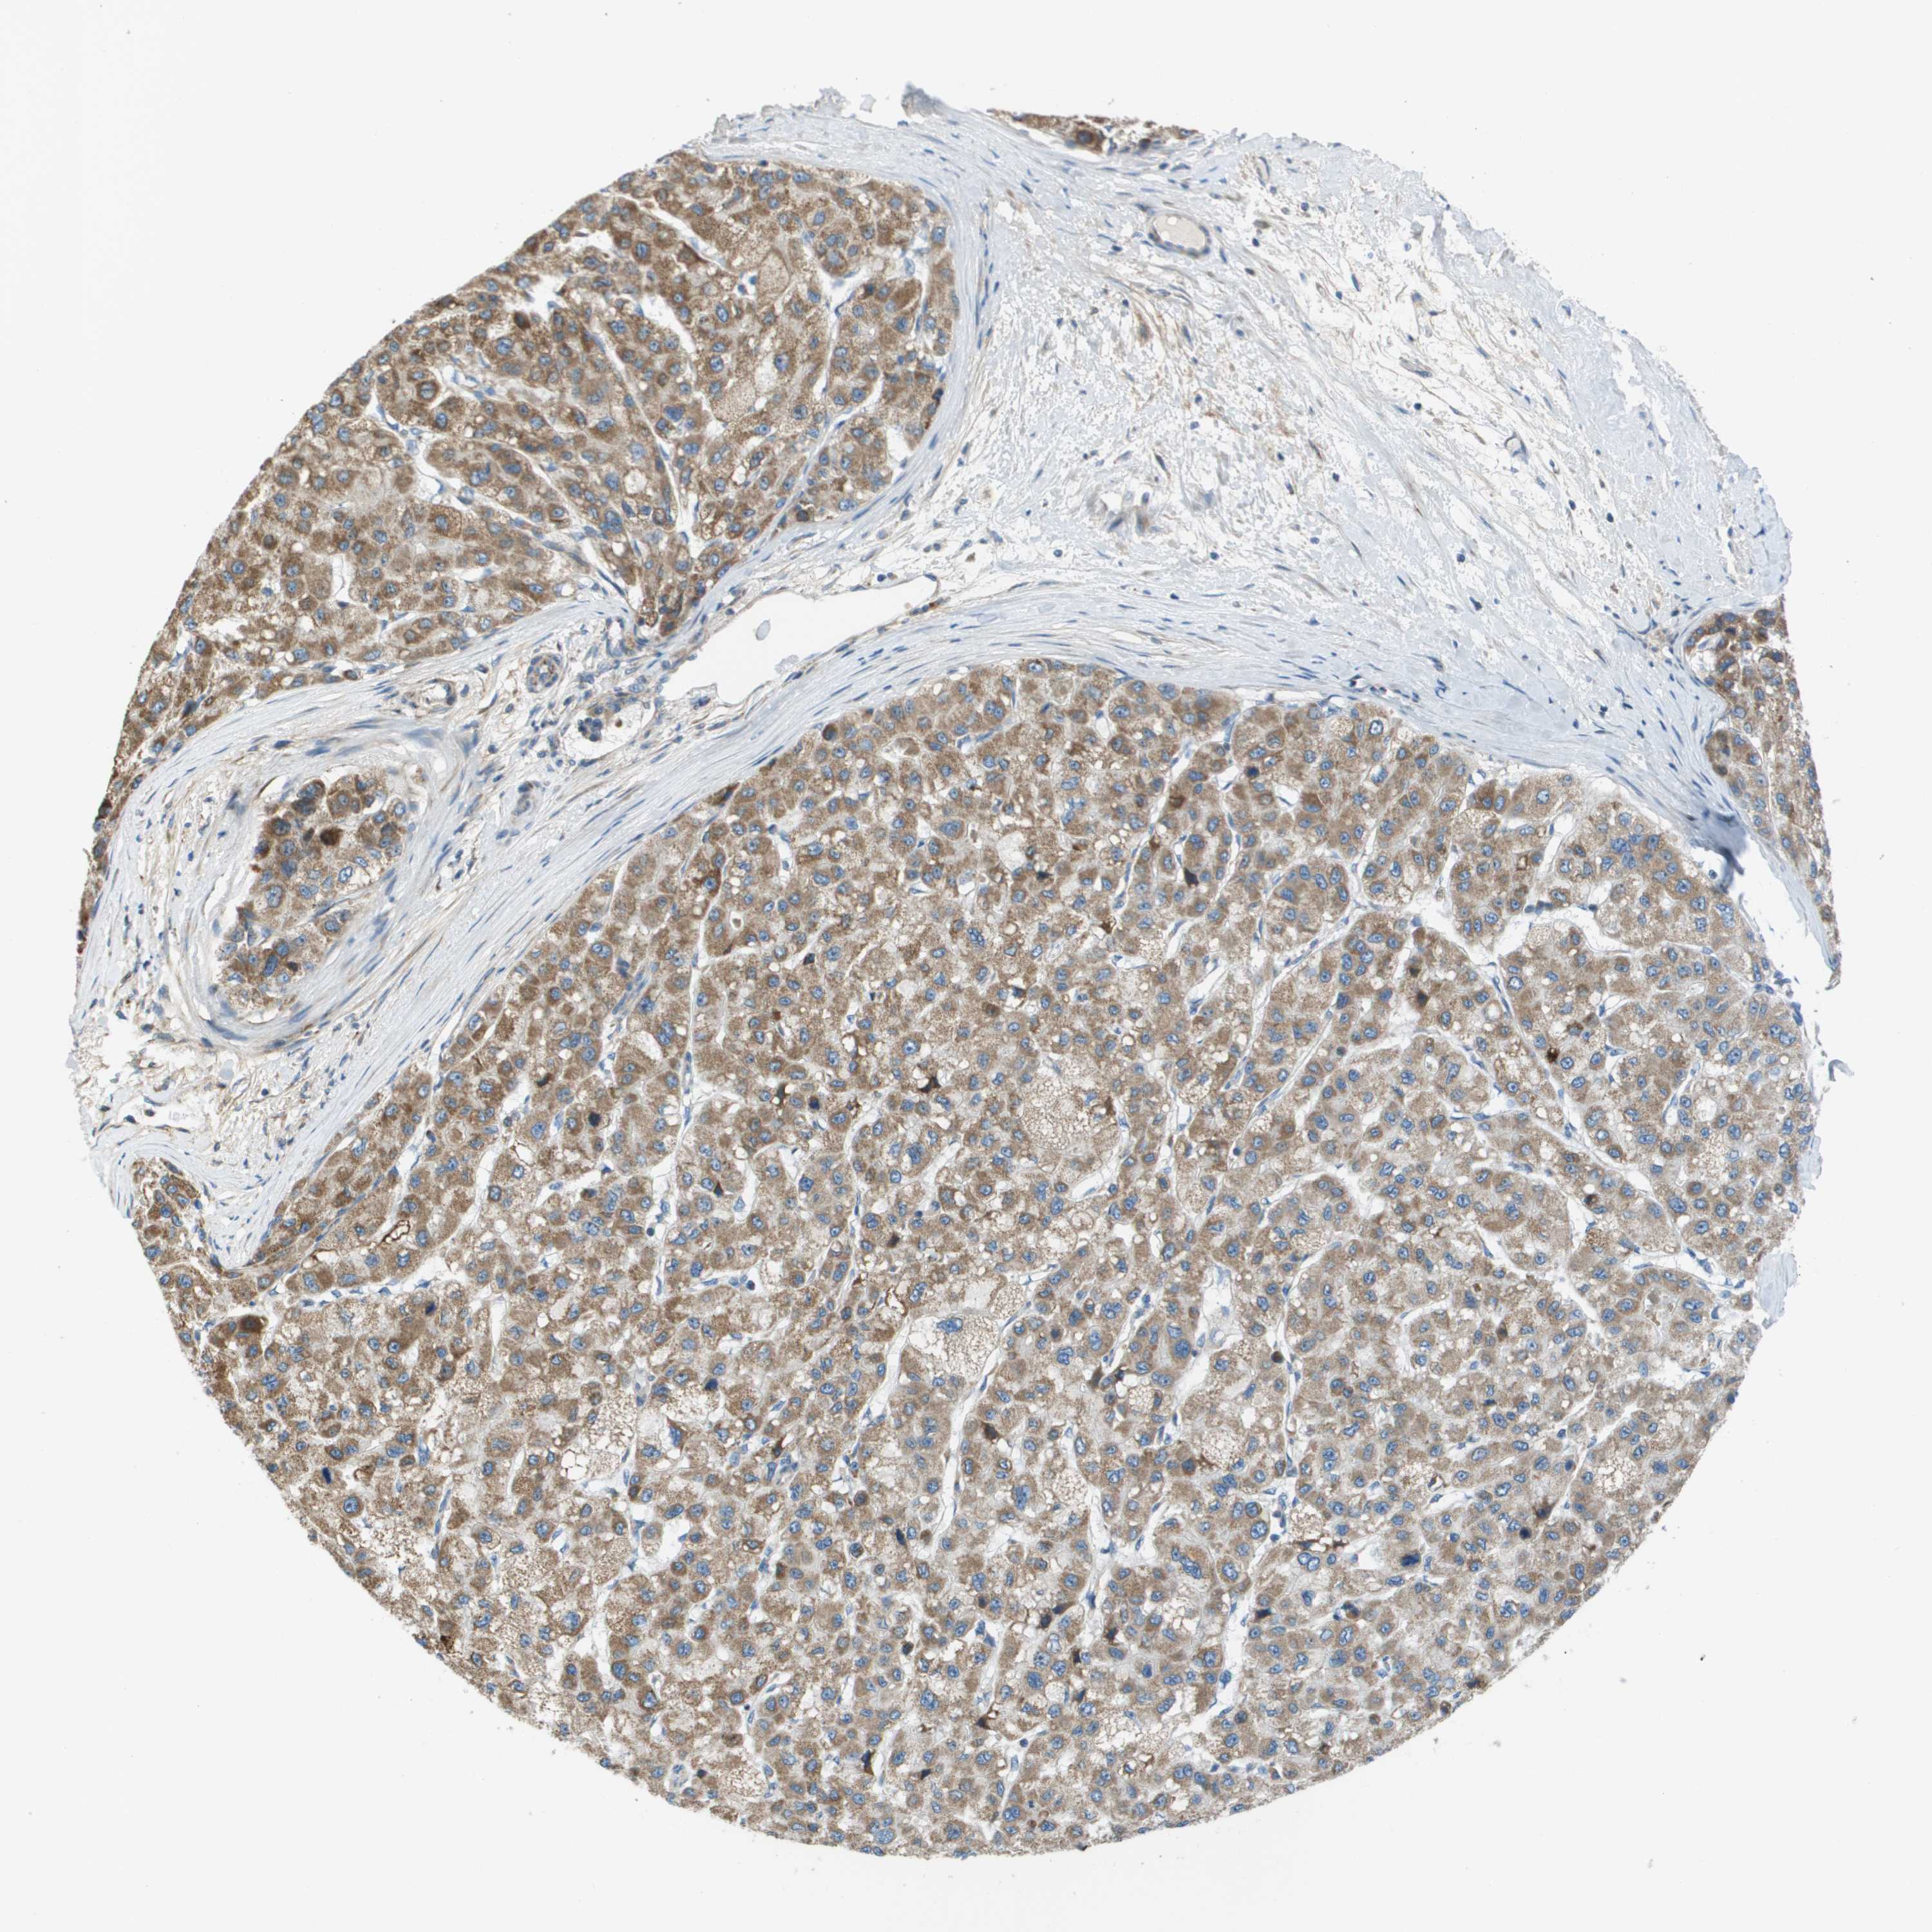

LIVER CANCER - Protein expressioni

A mouse-over function shows sample information and annotation data. Click on an image to view it in a full screen mode. Samples can be filtered based on level of antibody staining by selecting one or several of the following categories: high, medium, low and not detected. The assay and annotation is described here.

Note that samples used for immunohistochemistry by the Human Protein Atlas do not correspond to samples in the TCGA dataset.

Antibody stainingi

Antibody staining in the annotated cell types in the current human tissue is reported as not detected, low, medium, or high, based on conventional immunohistochemistry profiling in selected tissues. This score is based on the combination of the staining intensity and fraction of stained cells.

Each image is clickable and will lead to virtual microscopy that enables deeper exploration of all samples and also displays staining intensity scores, fraction scores and subcellular localization as well as patient and tissue information for each sample.

Antibody HPA011762

Antibody HPA017086

Staining

High

Medium

Low

Not detected

Intensity

Strong

Moderate

Weak

Negative

Quantity

>75%

75%-25%

<25%

None

Location

Nuclear

Cytoplasmic/membranous

Cytoplasmic/membranous,nuclear

Cholangiocarcinoma

Carcinoma, Hepatocellular, NOS